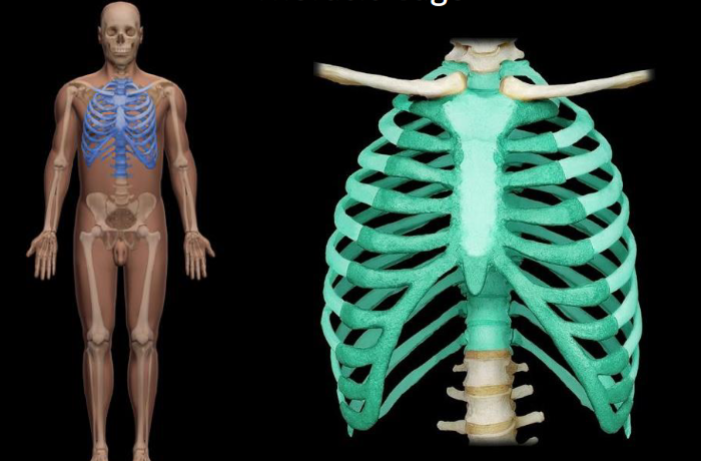

What bone is highlighted in this image?

rib cage (thoracic cage)

What bone is highlighted in this image?

costal cartilage (medial, touching the sternum)